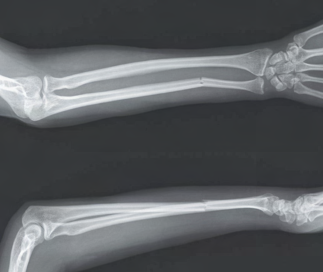

Recent studies indicate that Generative Pre-trained Transformer 4 with Vision (GPT-4V) outperforms human physicians in medical challenge tasks. However, these evaluations primarily focused on the accuracy of multi-choice questions alone. Our study extends the current scope by conducting a comprehensive analysis of GPT-4V's rationales of image comprehension, recall of medical knowledge, and step-by-step multimodal reasoning when solving New England Journal of Medicine (NEJM) Image Challenges - an imaging quiz designed to test the knowledge and diagnostic capabilities of medical professionals. Evaluation results confirmed that GPT-4V outperforms human physicians regarding multi-choice accuracy (88.0% vs. 77.0%, p=0.034). GPT-4V also performs well in cases where physicians incorrectly answer, with over 80% accuracy. However, we discovered that GPT-4V frequently presents flawed rationales in cases where it makes the correct final choices (27.3%), most prominent in image comprehension (21.6%). Regardless of GPT-4V's high accuracy in multi-choice questions, our findings emphasize the necessity for further in-depth evaluations of its rationales before integrating such models into clinical workflows.